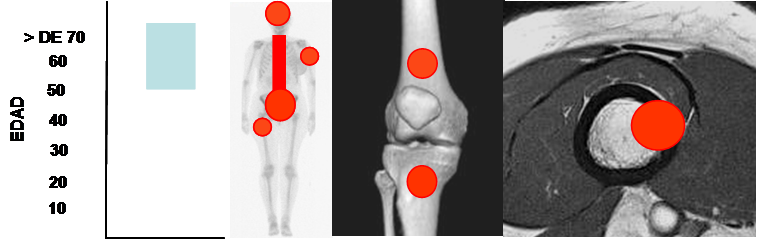

La mayoría afectan la columna, cráneo, pelvis y parte proximal de los huesos largos. Son muy raras en la parte distal, los codos y las rodillas. (3, 57). (Fig 222).

Fig 222. Metástasis.

Mayor frecuencia en adultos mayores. Predominio en columna, huesos planos y parte proximal

de los huesos largos. Lesión metafisodiafisiaria, de ubicación cortical o excéntrica.